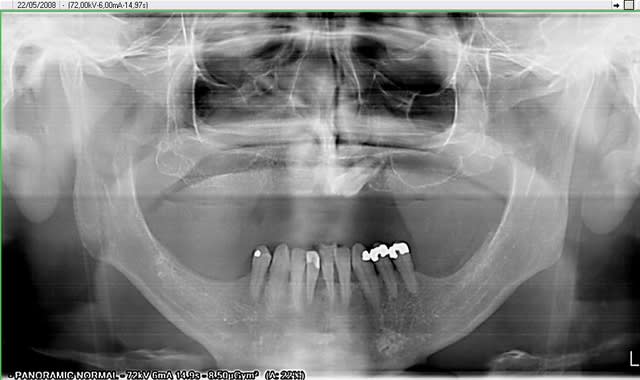

la pano post op

j'avais prévu de faire une MCI mais le manque de stabilité primaire des 2 implants côté droit m'en a dissuadé.

membrane biomend extend stabilisée par 2 petites vis de 4 mm de long de chez esasy implant. Os autogène et un peu de bio-os mélangé pour combler le defect.

dis donc growly, la fléchette en 34 a raté de peu sa cible !

"dis donc growly, la fléchette en 34 a raté de peu sa cible"

caramba, encore raté :) je visualise l'émergence du trou mentonnier et ai sondé pour voir s'il n'y avait pas de boucle antérieure. Du côté droit, il m'étais plus aisé de poser l'implant provisoire entre les implants.